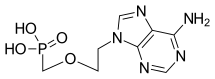

| Formula | C8H12N5O4P |

| Molar mass | 273.189 g·mol−1 |

SMILES

InChI

Adefovir dipivoxil contains two pivaloyloxymethyl units, making it a prodrug form of adefovir.